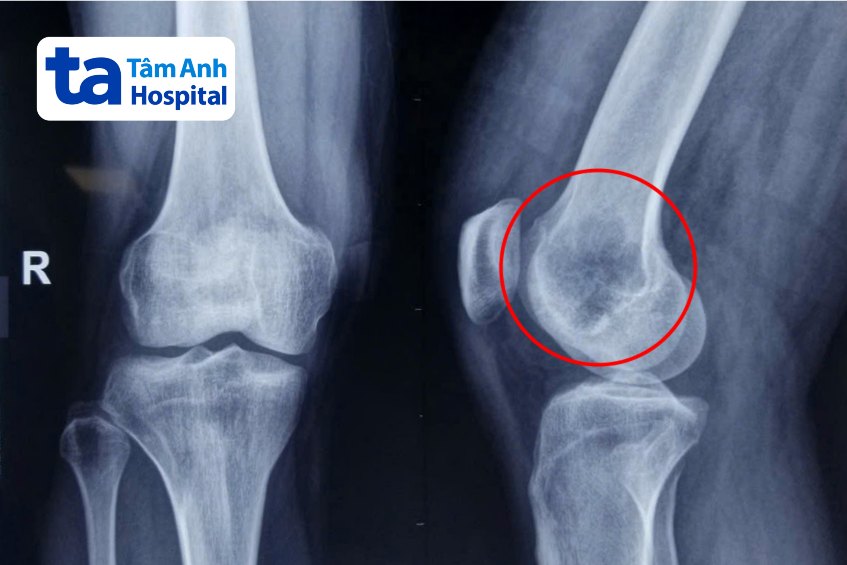

Sau hội chẩn sâu, nghi ngờ có bệnh lý tiềm ẩn phối hợp, anh Tài được chỉ định tầm soát xét nghiệm đo nồng độ FGF23 trong huyết thanh tăng cao kết hợp chụp PET/CT với chất đánh dấu Ga-68 DOTATATE khảo sát toàn thân. Kết quả xác định người bệnh có u với khối u ẩn ở vùng lồi cầu xương đùi phải, kích thước 32 x 25 x 42 mm, sau sinh thiết chẩn đoán xác định là U trung mô phosphaturic.

Anh Tài được bác sĩ chỉ định phẫu thuật nạo lấy khối u lồi cầu trong xương đùi phải kết hợp mài cao tốc tăng cường giúp giảm thiểu nguy cơ tái phát bướu. Sau đó đổ xi măng sinh học lấp khuyết hổng lớn mà khối u để lại và tái tạo lại vùng lồi cầu đùi bằng vách vỏ xương mào chậu cùng bên. Phương pháp này giúp giữ lại nguyên vẹn chi thể và hình dạng khớp gối bình thường cho người bệnh, bảo tồn chức năng vận động chi thể.